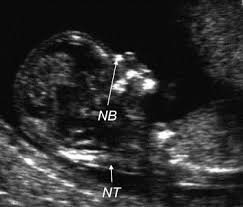

A Review On Techniques For Computer Aided Diagnosis Of Soft Markers For Detection Of Down Syndrome In Ultrasound Fetal Images Biomedical And Pharmacology Journal

Examples Of Nasal Bone Length And Prenasal Thickness Measurements Download Scientific Diagram